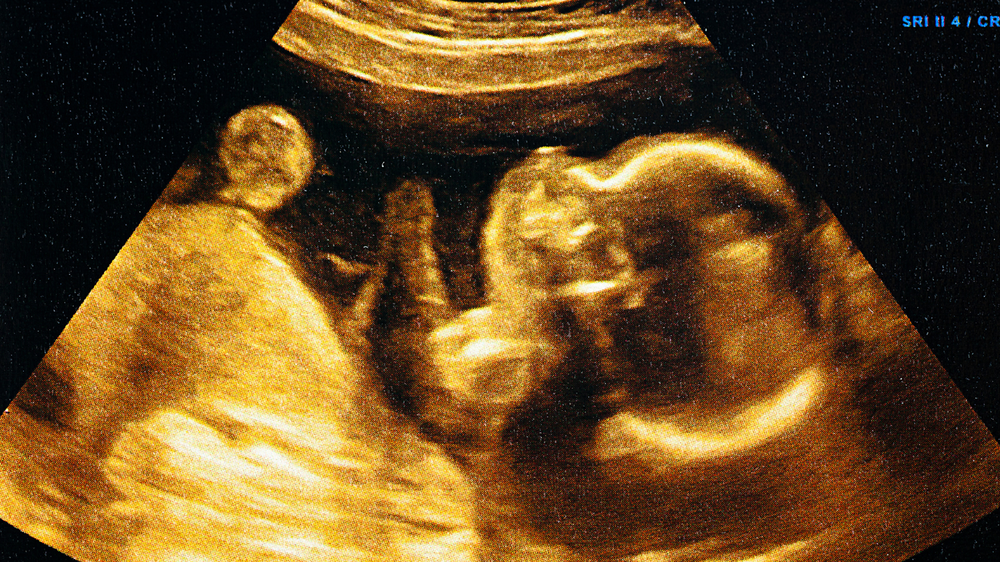

Feeling your baby move is the most exciting part of a pregnancy, and it feels so special when it's the first time. Those tiny flutters are also a sign of reassurance that your baby is doing fine. You may notice these movements become distinct and sometimes quite strong as your pregnancy advances.